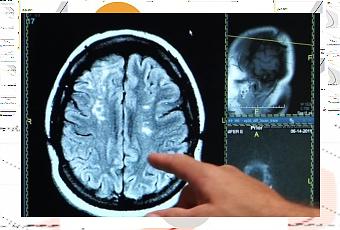

Les chercheurs de l’Université de Göteborg (Suède) et de l’University College London ont suivi durant 5 années, 700 femmes âgées de plus de 70 ans, exemptes de démence, dont 98 prenaient des suppléments de calcium. Au cours du suivi, ces participantes ont subi des tests d’imagerie afin de détecter les signes de maladie cérébrovasculaire, des lésions de la substance blanche ou les zones du cerveau ayant une mauvaise circulation sanguine- ce qui est associé à la démence vasculaire. Au cours du suivi,

La supplémentation en calcium déclencheur d’AVC chez les femmes déjà à risque élevé : Enfin, une analyse plus poussée montre que la prise de calcium n’a pas augmenté le risque de démence chez les femmes qui avaient pas eu d’AVC ou qui ne présentaient aucun signe de lésions de la substance blanche sur leurs scans du cerveau. L’analyse révèle que l’augmentation du risque de démence est concentrée chez les femmes sous supplémentation, à antécédents d’accident vasculaire cérébral, ou présentant déjà des signes de dommages aux vaisseaux sanguins dans le cerveau. Les résultats de cette étude observationnelle, mené sur un petit échantillon de femmes sous supplémentation, doivent être confirmés. Les chercheurs concluent ainsi : » La supplémentation en calcium peut augmenter le risque de démence chez les femmes âgées ayant une maladie cérébrovasculaire « . Cependant ces résultats alertent, une nouvelle fois, sur l’importance de discuter de telles supplémentations, qui ne sont pas anodines, avec le médecin traitant.